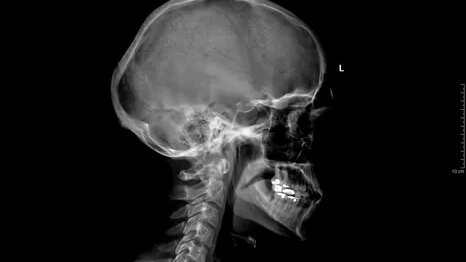

РЕНТГЕН ЧЕРЕПА ЧТО ЭТО Рентген черепа — это 2-х мерное рентгеновское исследование, проводится в двух проекциях (прямой и боковой). Снимок охватывает все кости черепа, включая верхнюю и нижнюю челюсть, а так же турецкое седло. ДЛЯ ЧЕГО Рентген черепа может быть назначен в следующих случаях: КАК ПРОВОДИТСЯ Пациента укладывают на специальный рентгеновский стол, снимок проводится в двух проекциях, прямая проекция — лежа на животе лицом вниз, боковая — то же на животе, только голова поворачивается на необходимый врачу бок...